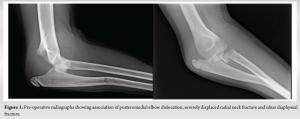

We report the case of an 11-year-old girl who fell from her height. She had a medical history of right elbow dislocation 3 years before. She had no other traumatic history. The patient tripped over a doorframe, fell, and landed on her right hand with an outstretched elbow. She went to the emergency room, where a radiograph was performed (Fig. 1). The radiograph showed an unusual association of posterior elbow dislocation, a grade 4b RNF (according to Judet), and a greenstick fracture of the proximal ulnar shaft. This association is not a terrible triad injury of the elbow as the coronoid is not injured and we have a RNF instead of a radial head fracture [1]. It is not a Monteggia association, as the ulna is not dislocated in the Monteggia.